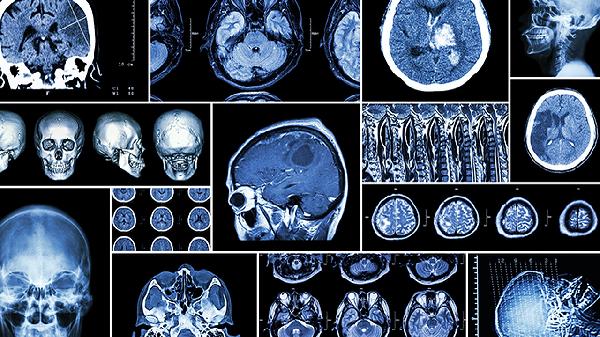

颅骨修补术前需进行头颅三维CT评估缺损范围,术后避免剧烈运动防止修补材料移位。日常建议高蛋白饮食如鱼肉、鸡蛋,配合维生素K丰富食材如菠菜促进凝血。恢复期进行颈部肌肉训练改善血液循环,睡眠时采用健侧卧位减少局部压迫。定期随访监测有无皮下积液或材料排斥反应,出现头痛加剧或发热需及时复查。